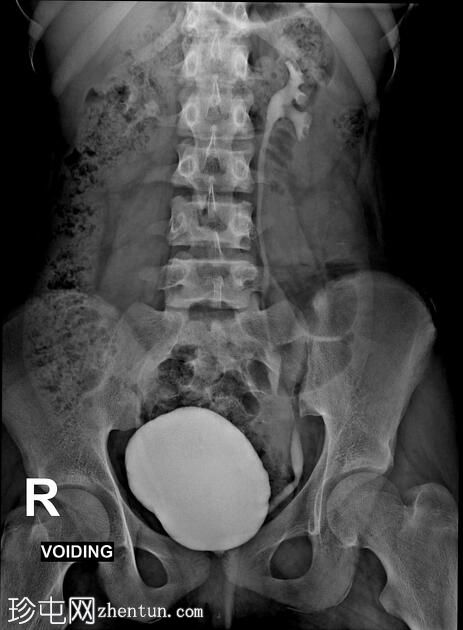

年龄:12岁

性别:女

透视检查

正位

排尿性膀胱尿道造影显示尿液反流至

肾脏

,伴有输尿管和肾盂肾盏系统轻度扩张。

还观察到排尿后残余尿。

本病例描述了一例有复发性尿路感染病史的儿童,其双侧3级膀胱输尿管反流。